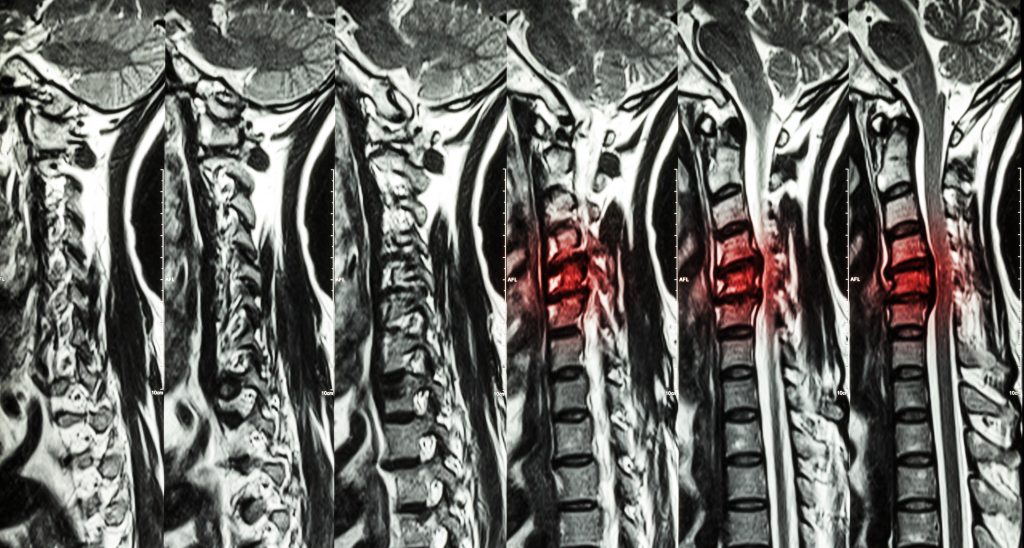

The only way to know you have a herniated disc with certainty is to be examined by a doctor. Your doctor will give you a physical examination in order to identify the source of your pain. In addition to nerve function and strength tests, your docto may using imaging tests to examine your spine in detail such as:

- X-Rays

- MRIs

- CT scans